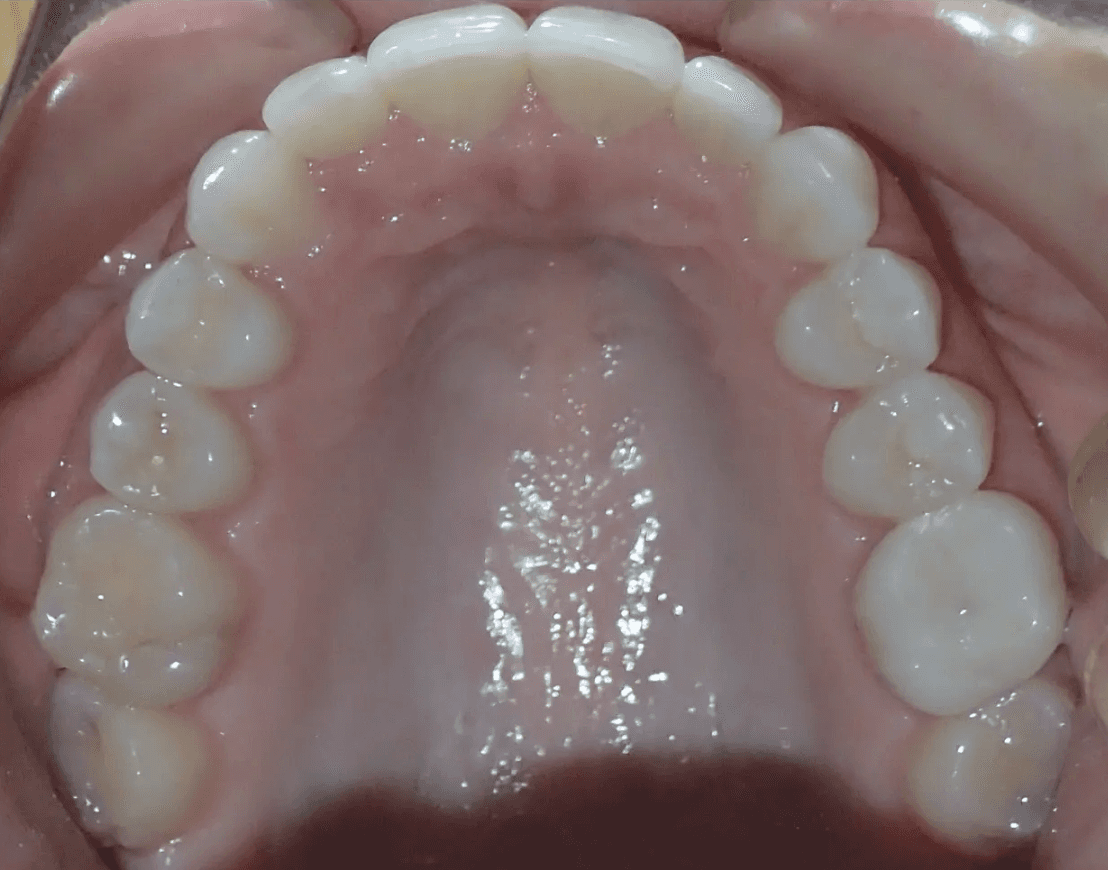

Final results

INTRAORAL